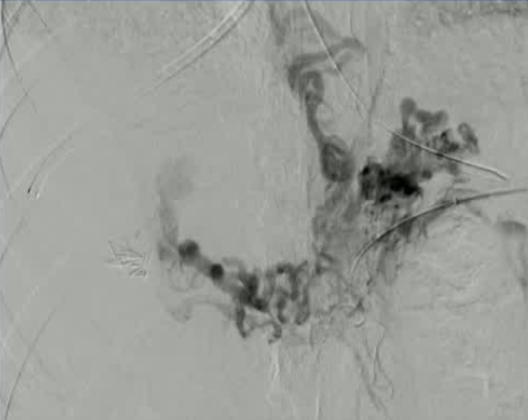

该程序包含以下步骤: 经脾脏入路:在超声引导下,刺穿脾静脉内的一个实质内分支。 在通过脾静脉造影确认了静脉通路后,导管和导丝被推进,以穿过脾静脉并抵达血栓化的门静脉。在门静脉/右门静脉分支处放置圈套器,为TIPS穿刺精准定位。TIPS穿刺圈套器,并穿过圈套器完成TIPS

步骤: 鉴于慢性血栓形成的复杂性: 一种经脾脏途径的门静脉再通术(PVR)。 随后是经颈静脉肝内门体分流术 。

结果:术后影像学检查显示门静脉和脾静脉的血流情况有所改善,且残留血栓极少。

通过经颈静脉肝内门体分流术(TIPS)治疗慢性门静脉血栓时所涉及的技术复杂性和决策难题,尤其是在标准方法因血栓程度过重而无法实施的情况下更是如此。 采用脾经脏穿刺术治疗门静脉高压症的方法证明能够有效克服这些难题,从而成功实施了经颈静脉肝内门体分流术(TIPS)。 PVR-TIPS 作为一线治疗方案:PVR-TIPS 为慢性门静脉血栓的治疗提供了一种技术上可行的解决方案,克服了标准 TIPS 安装所面临的难题。 持久效果:该干预措施不仅恢复了门静脉的血流,而且在后续随访中还显示出持续的通畅性以及血栓的完全消散。